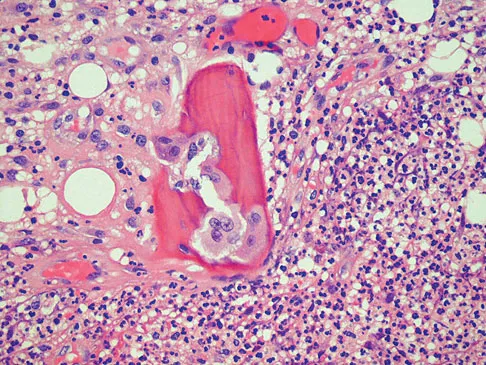

A 14-year-old boy has had knee pain for the past 2 months. He also has a low-grade fever of 101.3 degrees F (38.5 degrees C). Laboratory studies show a WBC count of 12,100/mm3 and an erythrocyte sedimentation rate of 58/h. A biopsy specimen of a lesion in the distal femoral metaphysis is shown in Figure 38. What is the most appropriate treatment?